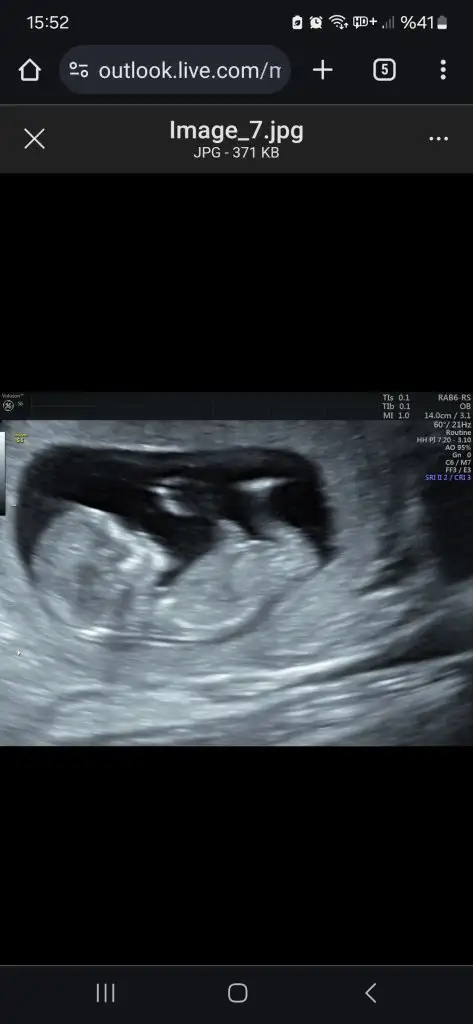

Erkek gibi canım12 haftalık tam orda görünen ayağı var mı tahminde bulunmak isteyen ?

Megi selam benimkide yukarıda rica etsem yorum yapar mısınErkek gibi canım